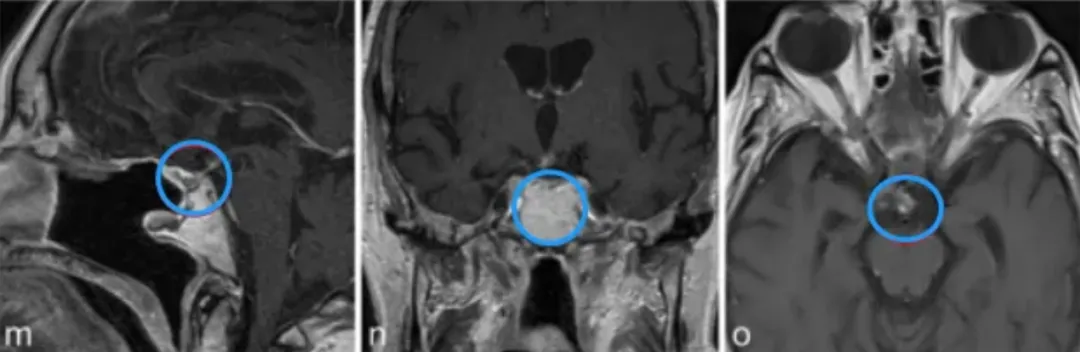

j-l图表示,在3个月后复查MR检查,显示术后垂体柄处有肿瘤少量残留。

m-o图显示,磁共振成像分期立体定向放射治疗后22个月,显示肿瘤明显缩小。病人经氢化可的松和甲状腺激素的替代治疗恢复良好。